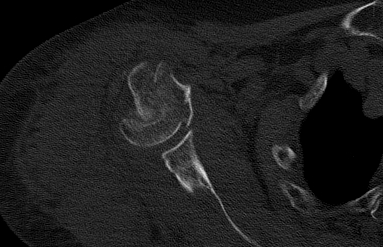

①术前肩关节X片

②肩关节CT示:肱骨近端粉碎骨折